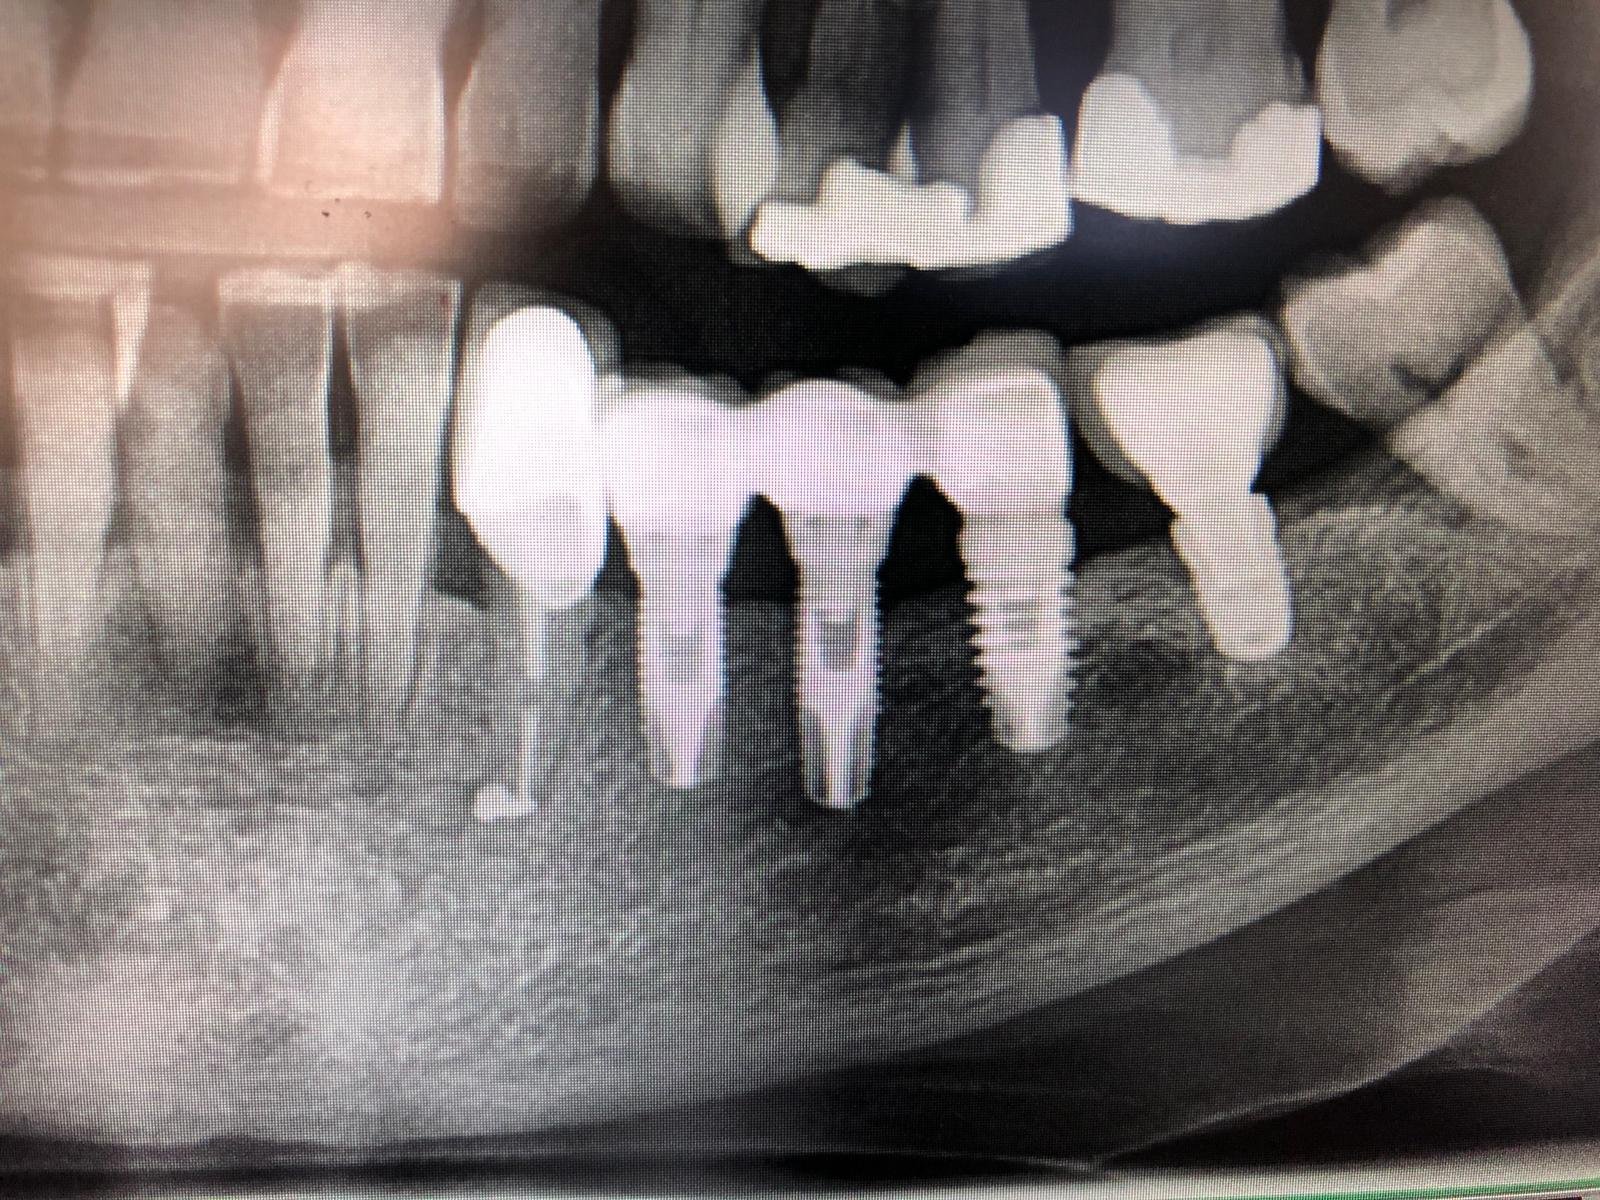

Esta paciente nos llega desde Rumania con un gran popurrí de implantes colocados y que usaremos para su rehabilitación oral. Estos dos no los tenemos identificados. Espero que me podáis [...]